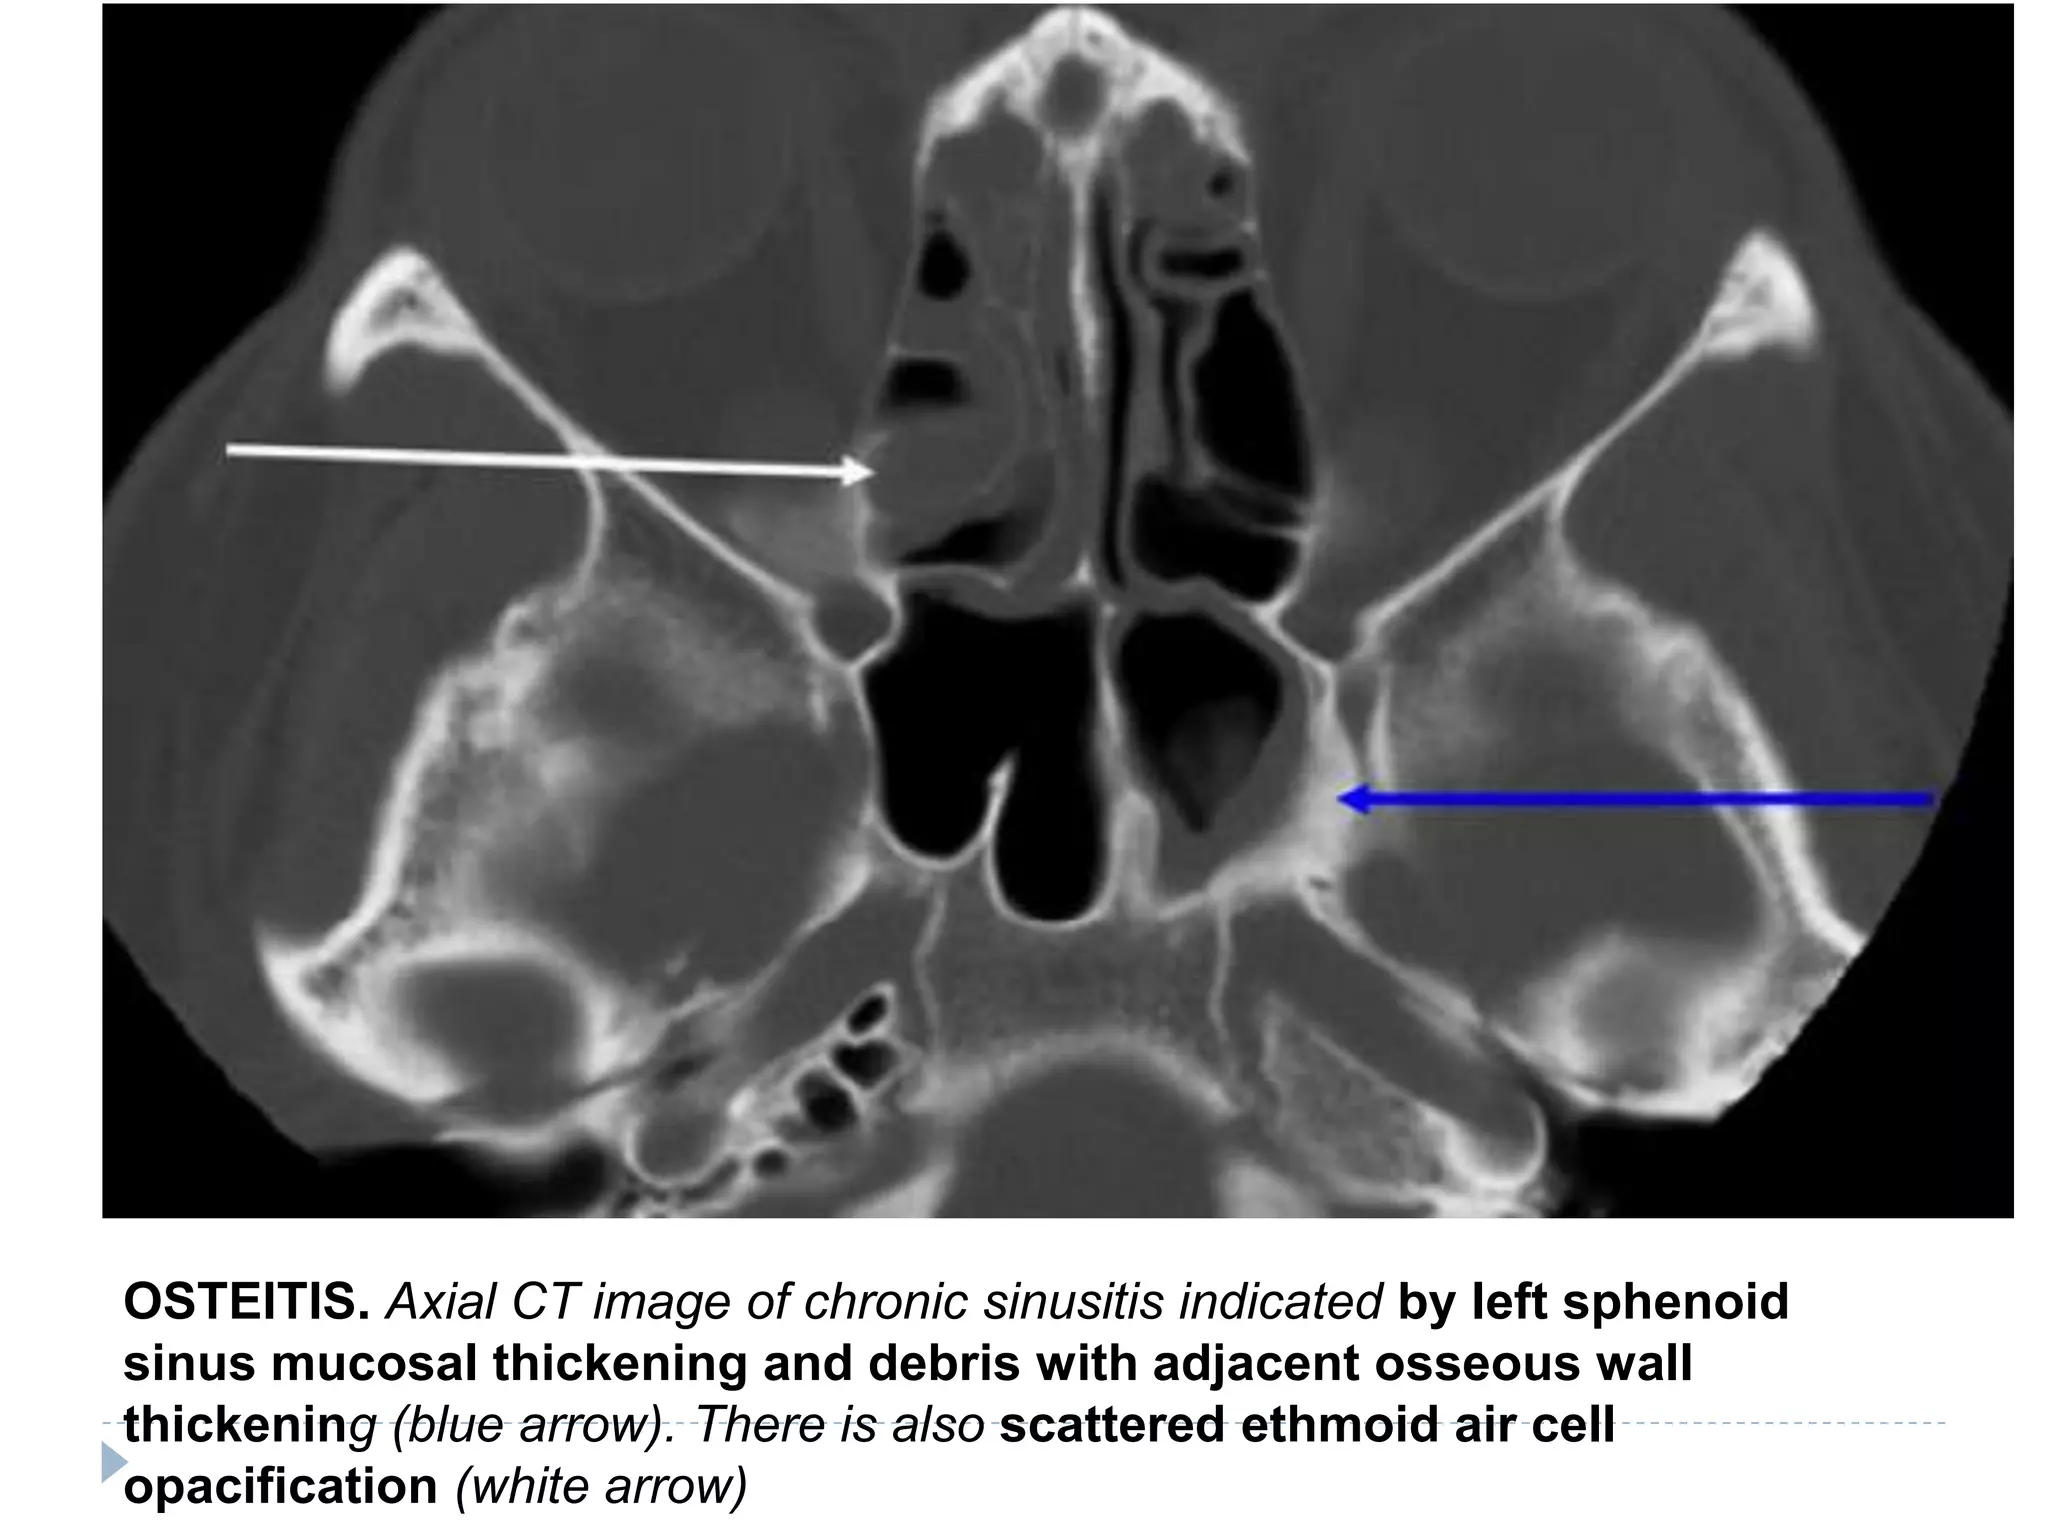

OSTEITIS. Axial CT image of chronic sinusitis indicated by left sphenoid

sinus mucosal thickening and debris with adjacent osseous wall

thickening (blue arrow). There is also scattered ethmoid air cell

opacification (white arrow)